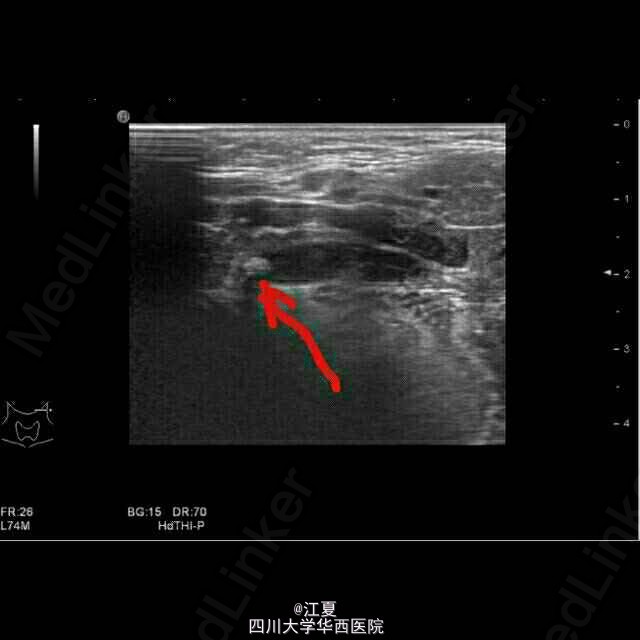

患者,女,19岁。发现颈部包块3月余。

包块无红肿,有轻微触痛。 超声示:左侧颌下腺长大,前后径约18mm,颌下腺导管增粗,最粗约5mm,内查见大小约4mm的强回声团伴声影。

诊断:左侧颌下腺导管结石伴扩张,左侧颌下腺长大。 治疗:摘除涎石(碎石机粉碎或手术)。症状较轻者可口服排石汤或其他辅助药物。预防应多饮水或进食酸性食品,促使唾液分泌,可使小涎石自行排出。